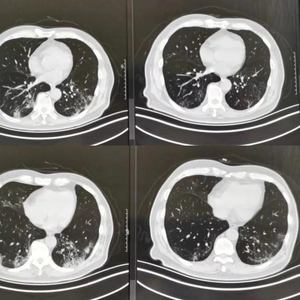

74岁的李老伯有30多年的吸烟史,既往有轻度的肺气肿,戒烟后他很注重锻炼,每天坚持万步走,平时身体也一直很好。然而,去年12月下旬感染新冠病毒后,他的两肺多发炎症,类似于“白肺”,当时紧急收入了胸科医院呼吸与危重症医学科病房。经过抗病毒治疗及密切监护,老伯咳嗽、胸闷及呼吸困难的症状日渐缓解,指脉氧饱和度也恢复正常。“阳康”后,他到院复查胸部CT,医生表示肺部病灶已经好转吸收,出现的部分肺间质改变也不用担心,这让老伯终于放下心来。

肺纤维化的发生机制很复杂,通常是在不同的诱因下,比如吸烟、空气污染、感染等因素,导致肺部成纤维细胞增殖及大量细胞外基质沉积并伴炎症损伤、肺间质组织结构破坏为特征的肺部病变。症状表现是咳嗽、胸闷、呼吸困难,活动后上述症状加重。胸部CT表现为两肺的磨玻璃影、实变影、网格影、蜂窝影、支气管扩张等。

对于这类感染相关肺纤维化患者,又分为两种情况,一种是感染后的间质性肺炎(或肺间质异常),就像上述李老伯的情况,表现为磨玻璃影、实变影,可以不需要额外治疗,也可以采用抗氧化治疗,3至6个月后再复查,基本就会慢慢吸收好转。另一种是感染后的肺纤维化,出现网格影、蜂窝肺,也不需要过分担心。目前对于感染后肺纤维化患者,主要采用抗炎、抗氧化的治疗,特别严重的,建议采用抗纤维化药物来治疗,多数在3至12个月也会慢慢好转。

有一部分患者平时不怎么咳嗽,这次感染后咳嗽时间长,症状始终未缓解,可以去做一下胸部CT检查。还有一部分“阳康”患者表现为胸闷、走路气喘,甚至动一动就出汗,有的可能还有低热,也应该查胸部CT看看肺部是否有炎症,同时需要验血查血常规、C反应蛋白等。如果胸部CT显示肺部存在磨玻璃影、实变影,甚至肺部纤维化,就提示存在感染后间质性肺病。